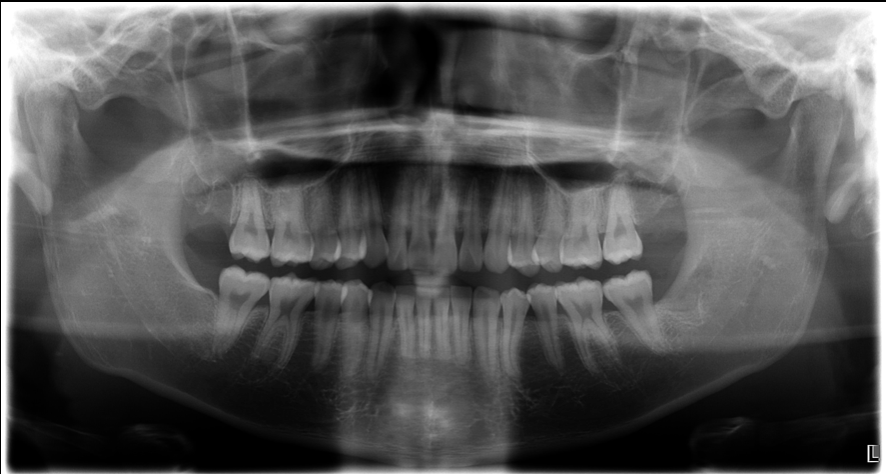

治療後

当院では、拡大視野での精密な処置により、可能な限り骨を削らず、歯だけを取り出す抜歯術式を採用しています。

無理に力を加えず、歯根の形や方向を的確に見極めてから、最小限の骨切削でアプローチします。

当院では、歯ぐきの切開範囲も最小限にとどめる「低侵襲アプローチ」を重視。

粘膜に余計なダメージを与えないことで、出血量も減り、回復もスムーズです。

だからこそ、当院では「ただ抜く」だけではなく、将来の歯ぐきや咬合(噛み合わせ)も見据えた親知らずの抜歯を行っています。